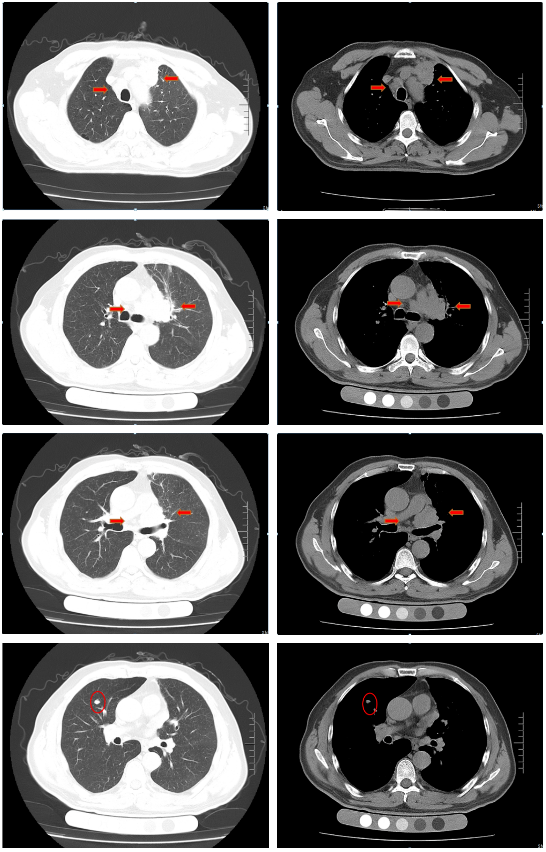

胸部增强CT(2022-02-12):左肺门及纵隔内见团块状软组织密度影,大小约62mm×42mm,边界不规整,内见血管影穿行,增强扫描呈轻度强化,局部支气管狭窄,远端肺内见片状磨玻璃密度影,边界欠清。右肺上叶见结节状密度增高影,较大直径约为8mm,增强扫描呈轻中度强化,右侧斜裂见长径约为6mm的高密度影,增强扫描未见明显强化;两肺透亮度增强,左肺下叶胸膜下囊状透光区。余气管、支气管通畅,未见明显狭窄、阻塞。纵隔和左肺门区见多发肿大淋巴结影,部分融合。两侧胸腔无明显积液。胸部CT诊断:左肺门及纵隔内占位,考虑肺Ca;纵隔及左肺门淋巴结肿大;右肺上叶结节,转移可能;右侧斜裂下结节;两肺肺气肿、左肺下叶肺大泡。

胸部CT(2022-04-12):左肺门及纵隔内见团块状软组织密度影,大小约57mm×37mm,边界不规整,局部支气管狭窄,远端肺内见片状磨玻璃密度影,边界欠清。右肺上叶见结节状密度增高影,较大直径约为9mm,右侧斜裂见长径约为7mm的高密度影;两肺透亮度增强,左肺下叶胸膜下囊状透光区;两肺可见索条状影。余气管、支气管通畅,未见明显狭窄、阻塞。纵隔和左肺门区见多发肿大淋巴结影,部分融合。两侧胸腔无明显积液。胸部CT诊断:左肺占位复查;纵隔及左肺门淋巴结肿大;右肺上叶结节,转移可能;右侧斜裂下结节;两肺肺气肿、左肺下叶肺大泡。

治疗后评价:经过EP方案治疗后两周期,患者仍有咳嗽、咳痰及左侧胸痛,症状无缓解,且出现体重下降;影像学检查提示左肺病灶及纵膈淋巴结及肺门淋巴结较前缩小不明显(缩小<30%),疗效评价SD。总体效果欠佳。

胸部CT(2022-07-15):双侧肺野透亮度增加,以两上肺和胸膜下明显。双肺纹理增多、增粗,紊乱,左肺上叶条片状高密度灶,大小约45mm×19mm,小叶间隔增厚。气管、左右主支气管无明显狭窄。纵隔内未见肿大淋巴结影。两侧胸腔无明显积液。胸部CT诊断:左上肺门占位复查;慢性支气管炎-肺气肿样改变。

治疗后评价:患者经过EP方案联合斯鲁利单抗治疗四周期后,患者咳嗽、咳痰及左侧胸痛症状消失,体重逐渐恢复;影像学提示左肺病灶及纵膈淋巴结及肺门淋巴结较前明显缩小(缩小>30%),右肺结节基本消失;疗效评价:PR(接近CR)。

胸部CT(2022-08-30):双侧肺野透亮度增加,以两上肺和胸膜下明显。双肺纹理增多、增粗,紊乱,左肺上叶见条片状高密度灶,大小29mm×18mm,小叶间隔增厚,两肺下叶见囊状透亮区。气管、左右主支气管无明显狭窄。纵隔内未见肿大淋巴结影。两侧胸腔无明显积液。胸部CT诊断:左上肺门占位复查;慢性支气管炎-肺气肿样改变;两肺下叶肺气肿。

治疗后评价:患者经过斯鲁利单抗单药维持治疗两周期后,患者未再出现咳嗽等症状,体重逐渐增加。影像学提示左肺病灶及纵隔淋巴结及肺门淋巴结、右肺结节基本消失,疗效评价接近CR。

病例小结

该患者为ⅣB期小细胞肺癌,一线采用标准化疗方案(EP)治疗2周期后疗效评估:SD,患者化疗敏感性不高;第二阶段治疗根据2022年CSCO小细胞肺癌诊疗指南,患者采用斯鲁利单抗联合EP方案,治疗2周期后体力状况明显改善,4周期后疗效评估:PR;第三阶段采用斯鲁利单抗单药维持治疗,2周期后影像学评估,左肺病灶及纵膈淋巴结及肺门淋巴结、右肺结节基本消失,疗效评估:接近CR。